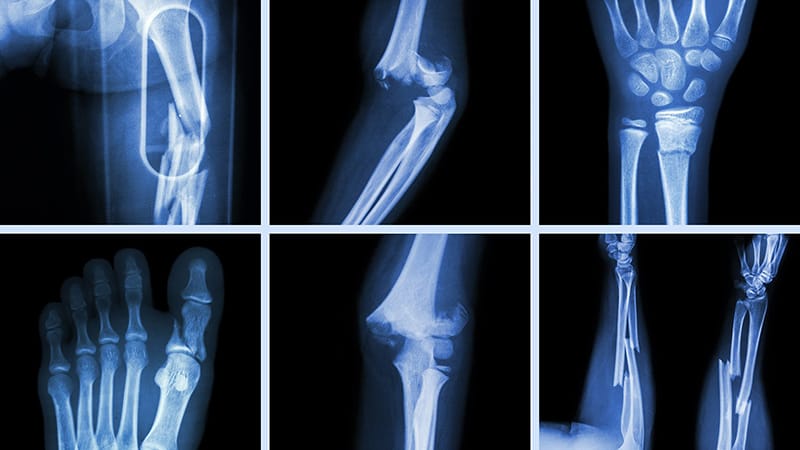

Gãy xương là tình trạng mà một hoặc nhiều đoạn xương trong cơ thể bị đứt gãy, rạn nứt hoặc vỡ hoàn toàn do tác động của một lực quá lớn, hoặc do cấu trúc xương bị suy yếu bởi bệnh lý nền. Khi xương bị gãy, tính liên tục của xương bị mất đi, dẫn đến sự mất ổn định trong cơ chế nâng đỡ và vận động của cơ thể. Tùy thuộc vào mức độ tổn thương, người bệnh có thể chỉ bị đau nhẹ hoặc có thể mất hoàn toàn khả năng cử động vùng bị chấn thương. Đặc biệt, nếu không được điều trị đúng cách, nguy cơ xảy ra biến dạng xương, mất chức năng, thậm chí là tàn phế là rất cao.

Chụp X-quang: Là kỹ thuật đầu tay trong chẩn đoán gãy xương. X-quang cho phép quan sát được vị trí gãy, đường gãy (ngang, chéo, xoắn…), tình trạng di lệch và số lượng mảnh xương. Hầu hết các trường hợp gãy kín, gãy di lệch đều được xác định rõ qua phim X-quang.